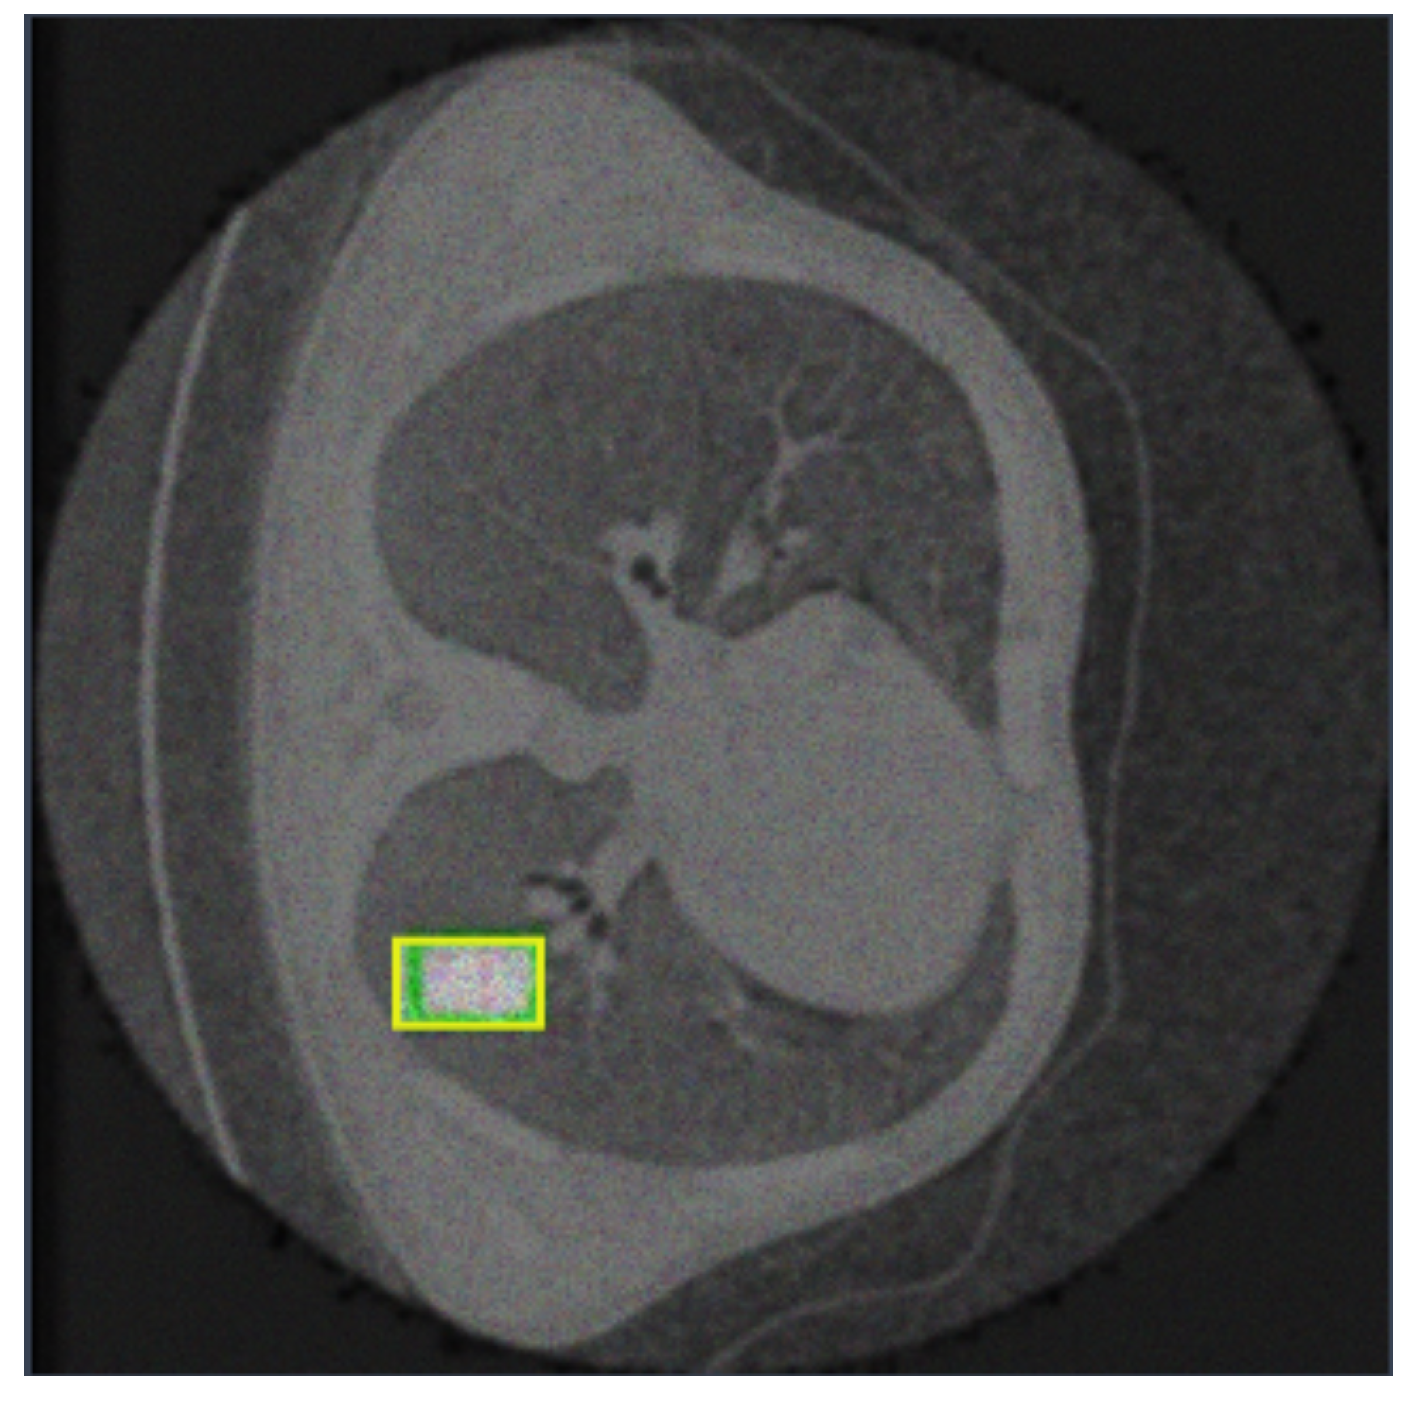

| Class | Image | Instances | Box (P) | Box (R) | Box (mAP50) | Box (mAP50-95) |

|---|---|---|---|---|---|---|

| all | 324 | 332 | 0.757 | 0.738 | 0.71 | 0.488 |

| adenocarsinoma | 324 | 45 | 0.815 | 0.685 | 0.713 | 0.492 |

| cancer | 324 | 46 | 0.572 | 0.783 | 0.588 | 0.467 |

| nodule | 324 | 241 | 0.884 | 0.747 | 0.831 | 0.505 |

| Class | Image | Instances | M (P) | M (R) | M (mAP50) | M (mAP50-95) |

| all | 324 | 332 | 0.75 | 0.733 | 0.708 | 0.438 |

| adenocarsinoma | 324 | 45 | 0.815 | 0.685 | 0.734 | 0.539 |

| cancer | 324 | 46 | 0.572 | 0.783 | 0.588 | 0.366 |

| nodule | 324 | 241 | 0.865 | 0.73 | 0.802 | 0.41 |